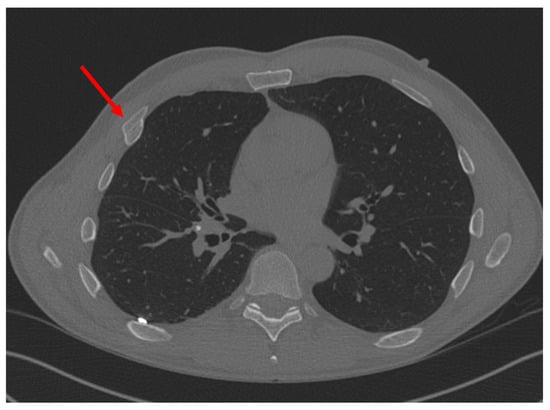

Figure 4.

Non-union fracture of the 7th rib. Red arrow points to the location of injury.